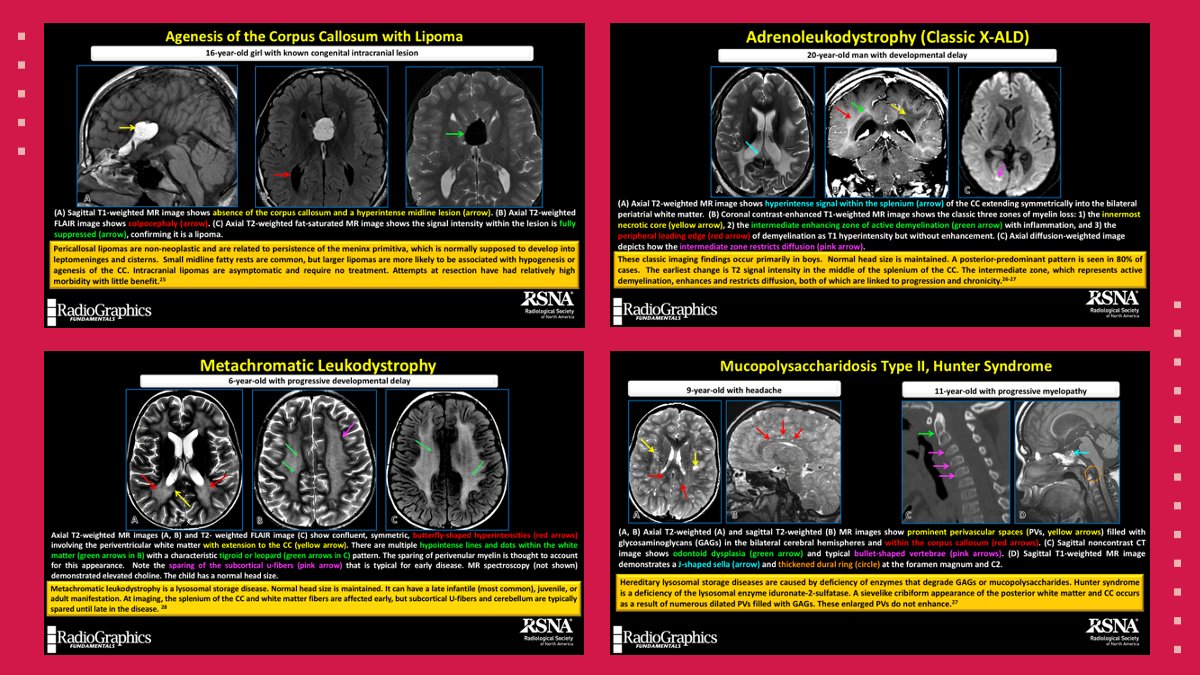

Congenital and genetic pathologies involving the corpus callosum include agenesis with lipoma, certain leukodystrophies, and Hunter syndrome.

#RGphx